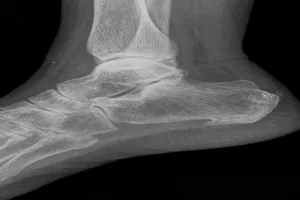

3. 석회화 건염

족저근막에 칼슘 침착이 생겨 통증을 유발합니다. 정확한 원인은 밝혀지지 않았지만, 퇴행성 변화와 관련이 있을 수 있습니다. 대부분 자연스럽게 호전되지만, 휴식, 냉찜질, 스트레칭, 체외충격파 치료, 스테로이드 주사 등을 시행할 수 있습니다.